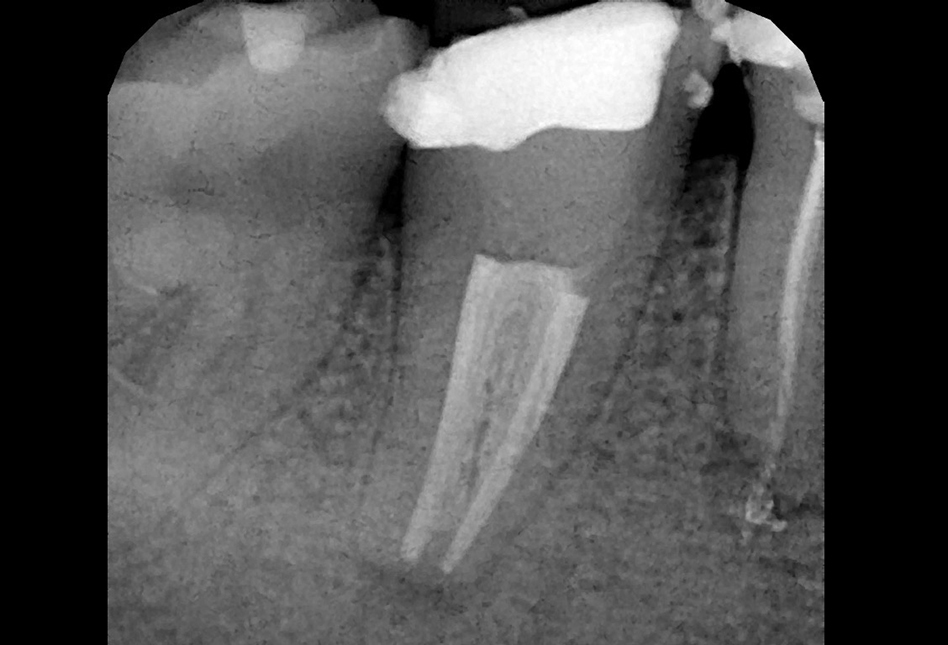

Zobe moramo zdraviti kadar pride do vnetja zobnega živca (pulpe) ali njegovega odmrtja (gangrena). Če kariesa ne odstranimo pravočasno, ta doseže zobni živec. To je lahko za vas popolnoma neboleče in brez težav, običajno pa se kaže s klasičnim zobobolom, ki se po moči lahko meri z najhujšimi telesnimi bolečinami. Zdravljenje zoba ponavadi zahteva več obiskov, ravno pri tem posegu pa je uporaba operativnega dentalnega mikroskopa najpomembnejša. Med zdravljenjem se poslužujemo tudi pomoči rentgenskih posnetkov, v zelo zahtevnih primerih pa tudi CBCT slikanja (cone-beam computed tomography – ali po slovensko – računalniška tomografija).

Granulom je kronično vnetje na koncu korenine zdravljenega ali gangrenoznega zoba. Vnetje povzročajo bakterije, ki so ostale v zobni korenini po zdravljenju. Skoraj 90% vseh granulomov ne povzroča bolečin. Zobozdravniki pa radi označujemo granulome z izrazom “tempirana bomba”. Granulom lahko namreč 10, 20 ali celo več let ne dela težav, počasi raste in topi kost, na enkrat pa izbruhne in vam začne delati ogromne težave. Glavne težave so bolečina, huda oteklina, vročina in splošno slabo počutje.Zato je nujno, da granulome opazimo pravočasno s pomočjo rentgenske diagnostike in jih skušamo s pomočjo endodontskega zdravljenja pozdraviti. Pogosto je ob izbruhu namreč edina rešitev odstranitev (puljenje) zoba.

Mnogo ljudi ima enega ali več zdravljenih zob. Zdravljenje zob je, zaradi komplicirane anatomije (zgradbe) zob, zelo zahtevno. Zato je žalostna resnica, da je večina zob, ki je bila zdravljena pred več kot 10 leti, zdravljena slabo. Take zobe je potrebno rentgensko kontrolirati, in v primeru, da opazimo na koncu korenin kronične spremembe, tudi ponovno zdraviti. Ponovno endodontsko zdravljenje lahko vključuje tudi poseg apikotomije. Če zdravljenje iz določenih razlogov ni možno, ni uspešno, ali pa je napoved izida zelo slaba, svetujemo odstranitev zoba in nadomeščanje z zobnim vsadkom ali mostičkom.